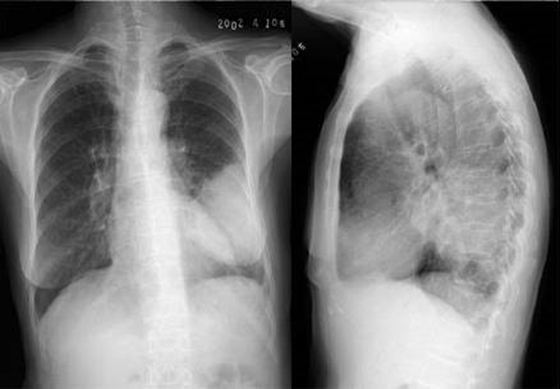

04卷-3.病史:男性,53岁,咳嗽、体重减轻4个月。诊断(本题满分2.00分)

C.左下肺癌

本题答案:C

题目解析:

【该题针对“X线-肺癌”知识点进行考核】